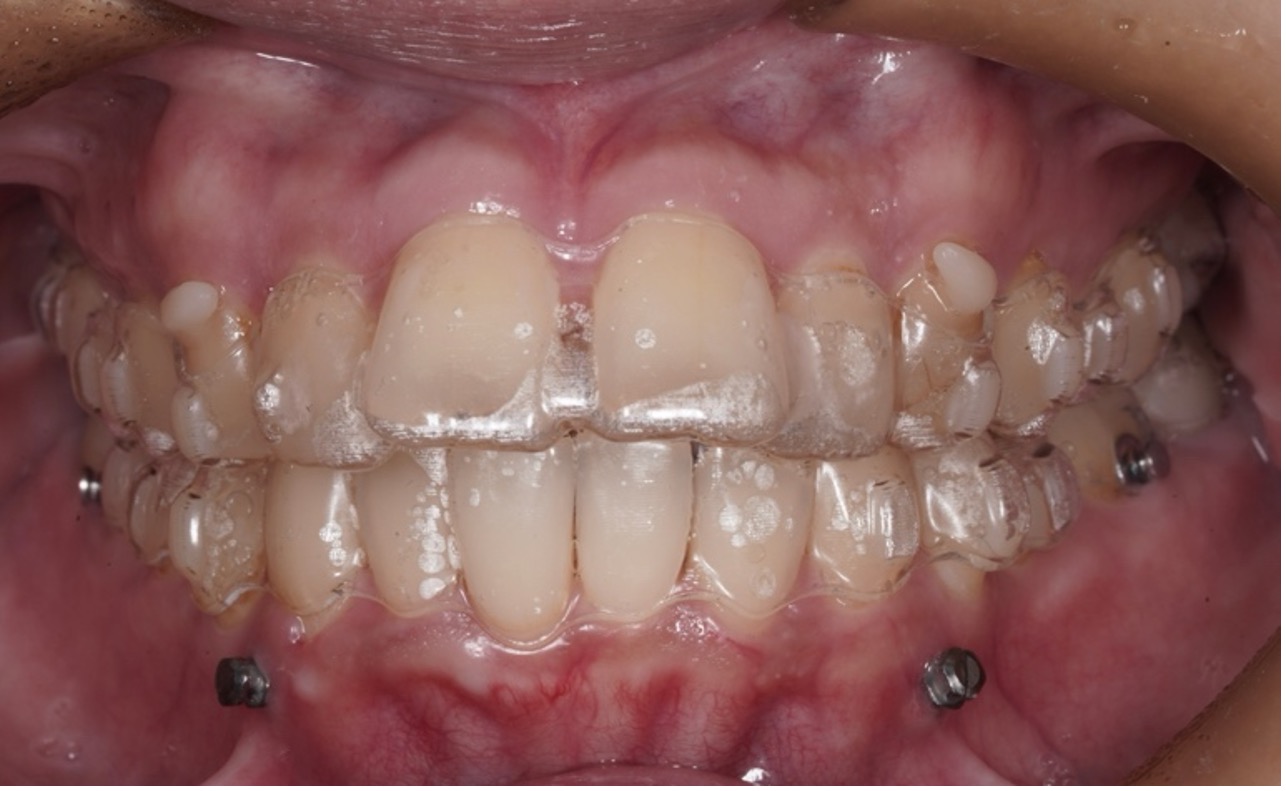

マウスピース矯正(インビザラインなど)は、透明なマウスピース型の装置を装着し、少しずつ歯を動かしていく矯正方法です。

「目立たず自然に矯正したい」という札幌駅前エリアの社会人・女性を中心に人気があります。

⚫︎透明で目立ちにくい:

接客・営業など人前に立つ仕事でも安心

⚫︎取り外しできて衛生的:

食事・歯磨きが普段どおり可能